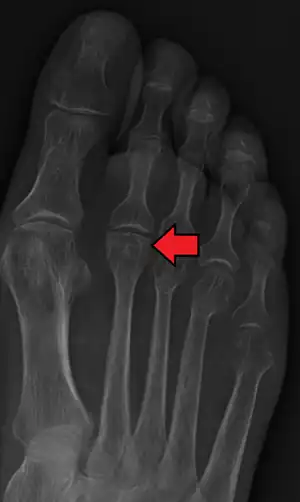

Freiberg disease as seen on plain film | |

Freiberg disease, also known as a Freiberg infraction, is a form of avascular necrosis in the metatarsal bone of the foot. It generally develops in the second metatarsal, but can occur in any metatarsal. Physical stress causes multiple tiny fractures where the middle of the metatarsal meets the growth plate. These fractures impair blood flow to the end of the metatarsal resulting in the death of bone cells (osteonecrosis). It is an uncommon condition, occurring most often in young women, athletes, and those with abnormally long metatarsals. Approximately 80% of those diagnosed are women. [1]